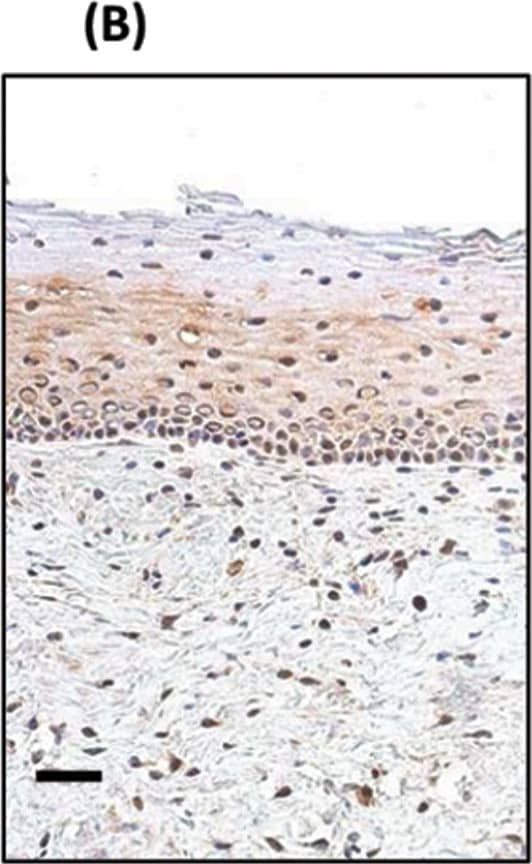

Detection of Human SOX2 by Immunohistochemistry

TP63 and SOX2 staining in cervical biopsies.Immunohistochemical staining of cervical biopsies. Bars = 50µm.(A) normal cervix no primary control; (B) normal cervix stained with anti-SOX2; (C) Squamous cell cervical carcinoma no primary control; (D) representative TP63, and (E) representative SOX2, staining of tumour cells. For both TP63 and SOX2 staining was seen in the nucleus of positive cells (examples indicated by solid arrows); negative cells were a minority of tumour cells (examples indicated by unfilled arrows). (F) Image analysis results of % nuclear +ve tumour cells in biopsies. Parallel sections from 11 cases were stained with SOX2 and TP63. Tumour cells were evaluated for their nuclear expression of the transcription factors. There was no significant difference between the data for SOX2 and TP63 (Wilcoxon signed rank test). Image collected and cropped by CiteAb from the following publication (https://pubmed.ncbi.nlm.nih.gov/25531390), licensed under a CC-BY license. Not internally tested by R&D Systems.